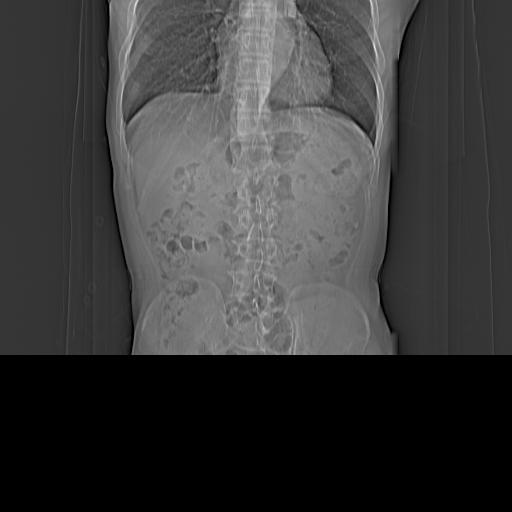

CT50974:请大家看看右肾有异常没有?

患者,男,52岁。自述咳血3天,余无自觉症状!!肺部感染病变!! 超声检查:右肾直径2.5cm低回声团块!!

左侧腰大肌肥厚,肠系膜增厚,腹内淋巴结增生,考虑肠系膜结核?

考虑肥大的肾乳头。建议增强或MRI